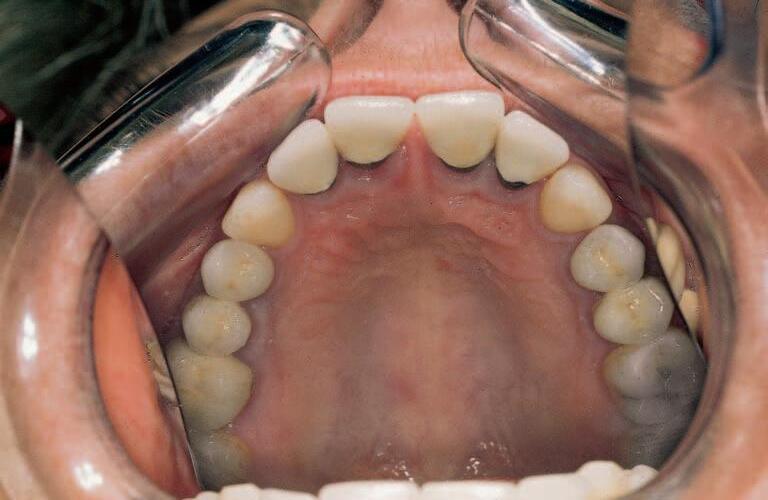

Obr.9 Studijnímodelpøedortodontickouterapiívdospìlosti

Obr.10 Stavzubníhoobloukupøedprotetickýmošetøením